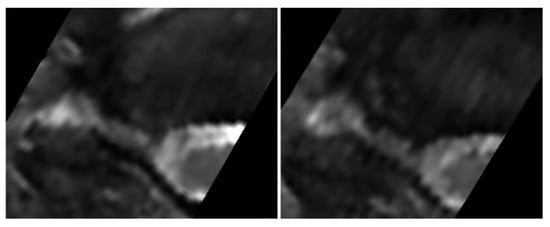

All patients were positioned without any complaints in the DMRICS apparatus, outside the MRI gantry. The patients were subsequently positioned within the MRI for a relaxed image acquisition. After successfully conducting the simulated Spurling test, immediate imaging was performed, which produced clinically acceptable image quality in 9 out of 10 patients in both relaxed and provoked positions, as shown in Figure 2 and Figure 3.

The significant increase in the qualitative gradings of the foramina when comparing MRI before and during the simulated Spurling test indicates that a Spurling test leads to higher Park and Kim grades. This offers not only insights into the variations of the often-employed clinical Spurling test but also suggests a possible clinical utility for dynamic MRI. The method could help in determining the severity of foraminal stenosis and identifying the impacted nerve roots if they are not distinctly discernible in a routine, relaxed MRI, especially when several foramina are narrow on a routine MRI and the symptoms and clinical examination cannot discriminate which nerve root(s) are giving rise to the experienced pain. However, for the foraminal area and cross-distance measures, no significant changes were detected in the present work. The reason for these contradictory findings may be that the foraminal shape shifts with compression and thereby the nerve compression may increase, even if the overall area is not changed or even increases; see Figure 2 and Figure 3. Further, the magnitude of measurement error in such small structures, especially for the axial-cross-distance measurements may also play a role here.

Figure 3. The (left) image shows the transverse plane in a relaxed position compared with the (right) image taken during the Spurling test.